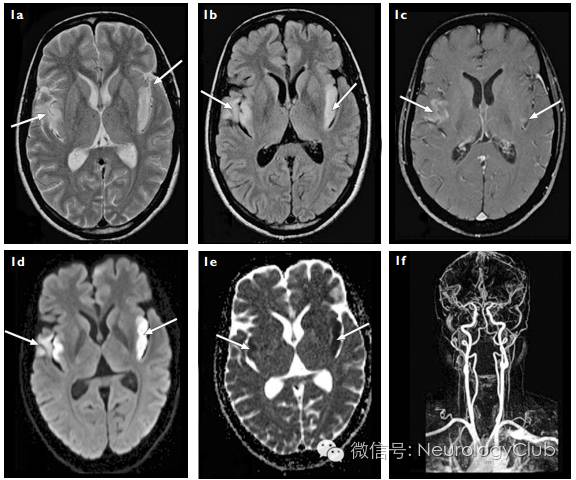

(图5:A-B:T2WI/FLAIR上可见双侧岛叶皮层高信号[箭];C:增强后右侧病灶强化,左侧无;D-E:DWI和ADC提示弥散受限;F:MRA正常)